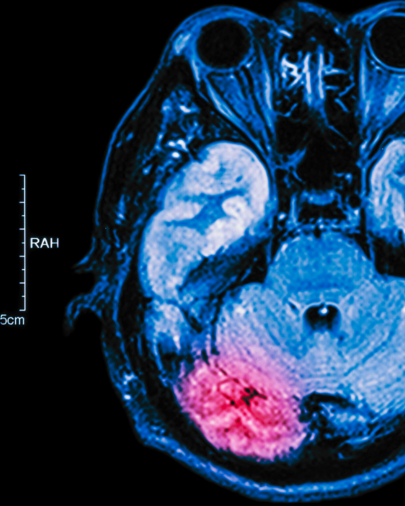

Teste: Confira se você reconhece um AVE no dia a dia

Escala de Cincinnati: O “Padrão Ouro” da agilidade no atendimento

Se tem uma ferramenta que todo profissional da saúde precisa ter na ponta da língua (seja você enfermeiro, técnico, fisio ou médico) é a Escala de Cincinnati (ou Cincinnati Prehospital Stroke Scale).

Ela foi desenhada para ser simples, rápida e, acima de tudo, eficaz. O objetivo não é dar um diagnóstico definitivo (isso a tomografia faz), mas sim identificar em segundos se aquele paciente tem uma alta probabilidade de estar sofrendo um AVE.